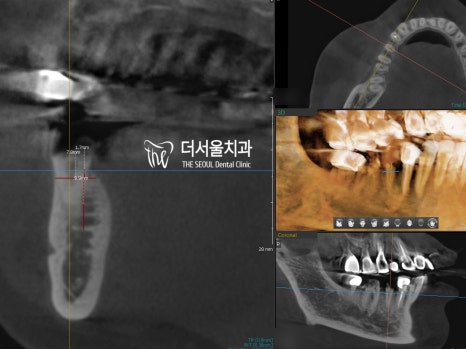

방사선 사진에서 검게 보이는 곳들이

다 심하게 썩어 버린 곳들이죠.

문제는 한곳이 아니라 소구치와

그 옆에 있는 대구치 한 곳까지

우식이 심하게 이어졌다는 것인데요.

CT 분석으로 잔존골의 양과 질을 고려하여

식립 위치를 결정한 뒤 발치를 진행했습니다.

이후 정해진 위치에 임플란트를 심어드렸는데요.

분석 위치에 딱 맞게 심어져 있는

모습을 확인할 수 있습니다.

좌측이 전, 우측이 후 사진인데,

정말 싱크로율 100%네요.